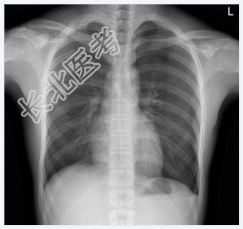

- [材料题] 男性,19岁,突发左胸痛2小时入院。查体.左侧呼吸音减低,深呼吸疼痛加剧,未闻及干湿性啰音。心脏体查无异常。做胸部X光平片检查。

- 简答题1、请问该患儿诊断是什么?

- 简答题2、左侧气胸的常见病因有哪些?

- 简答题3、左侧气胸的典型临床表现是什么?

- 简答题4、左侧气胸的治疗原则及方法有哪些?